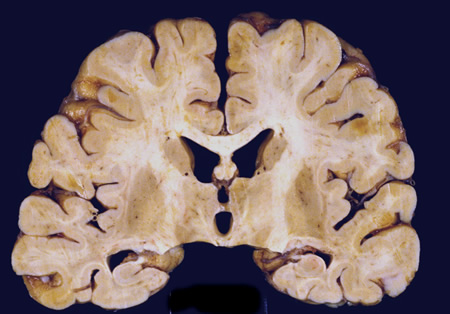

Corte coronal do cérebro de paciente com vírus da imunodeficiência humana (HIV) aos 30 anos. Ele tinha encefalite por HIV subaguda envolvendo tanto a substância branca quanto a substância cinzenta de forma difusa. Os ventrículos estavam aumentados refletindo substância branca e perda cortical

Do acervo pessoal de Robert E. Schmidt; usado com permissão